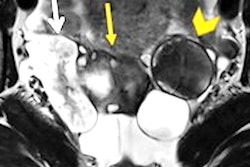

Mucinous borderline tumor and stage IA invasive ovarian cancer in a 28-year-old woman. Coronal T2 (a) demonstrates a large multilocular cystic mass of the right ovary typical of a mucinous tumor. At its superior aspect areas with irregular septations, contrast enhancement (b), and restricted diffusion (c) are demonstrated (arrow).

Time-intensity curves of the uterus (orange) and solid tissue of the mass (blue) demonstrate type 2 curve with typical initial rise followed by a plateau. At histopathology, in this area, foci of invasive cancer were seen. Images courtesy of European Radiology.Early detection remains one of the unmet needs in the management of this disease. Transvaginal sonography and MRI are effective tools to characterize ovarian masses, and greater standardization of imaging technique and implementation of predictive models of risk of malignancy can contribute to better detection, Forstner added.